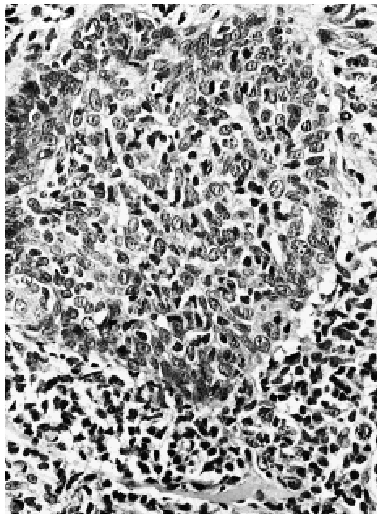

Fig. 4.--Imagen a gran aumento con los linfocitos atípicos distribuidos alrededor de restos de folículo, con intensa permeación del mismo (hematoxilina-eosina).

Una biopsia tomada de una de las placas de alopecia mostraba en dermis reticular un denso infiltrado linfoide atípico con células cerebriformes dispuestas exclusivamente alrededor de folículos pilosos, con permeación folicular (figs. 2, 3 y 4). En estas estructuras se advertían pequeños microabscesos, así como células atípicas aisladas con halos perinucleares. No existía mucinosis folicular y la epidermis suprayacente no mostraba epidermotropismo. El estudio inmunohistoquímico fue intensamente positivo para CD3, CD43 y negativo para CD79 alfa y CD20. Una biopsia de la adenopatía inguinal demostró infiltración ganglionar específica por linfoma cutáneo.

Histológicamente la MFF presenta un denso infiltrado de linfocitos atípicos rodeando y penetrando en los folículos pilosos, pero respetando generalmente la epidermis. Las características morfológicas e inmunohistoquímicas son indistinguibles a las de la MF clásica3, 12, 14-15. Para algunos autores no debe existir mucinosis folicular asociada16-18. Debido a la localización perifolicular de los infiltrados dérmicos se considera que los pacientes con MFF se encuentran en un estadio tumoral de su enfermedad2.